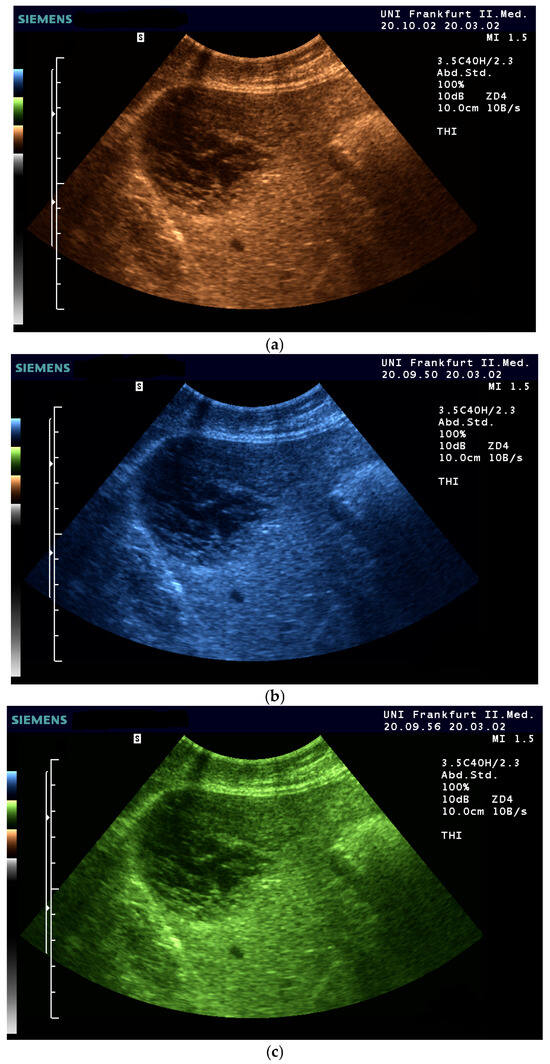

- The combination with speckle filters available in all high-end devices, similar to the low-pass filters used by Bleck et al. (1994) for tissue visualization [5], also yields significantly improved visualization results (Figure 5, Figure 6 and Figure 7). In principle, applications with new visualized texture analyses, such as random field models, are also conceivable [76,77].

- Fischer, T.; Filimonow, S.; Taupitz, M.; Petersein, J.; Beyersdorff, D.; Bollow, M.; Hamm, B. [Image quality and detection of pathology by ultrasound: Comparison of B-mode ultrasound with photopic imaging and tissue harmonic imaging alone and in combination]. Rofo 2002, 174, 1313–1317. [Google Scholar] [CrossRef] [PubMed]

- Merkel, D.; Brinkmann, E.; Kammer, J.C.; Kohler, M.; Wiens, D.; Derwahl, K.M. Comparison Between Various Color Spectra and Conventional Grayscale Imaging for Detection of Parenchymal Liver Lesions With B-Mode Sonography. J. Ultrasound Med. Off. J. Am. Inst. Ultrasound Med. 2015, 34, 1529–1534. [Google Scholar] [CrossRef]

| Color | Advantages |

|---|---|

| Sepia (Yellow-Brown) | Mimics familiar tones from black-and-white photography |

| Enhances contrast while preserving anatomical detail | |

| Offers intuitive brightness mapping (lighter tones = more echogenic areas) | |

| Preferred by students and experts alike | |

| Blue | Provides excellent depth perception |

| Reduces visual fatigue by avoiding glare and high saturation | |

| Often favored by experienced examiners for high-resolution detail | |

| Facilitates alertness and performance on tasks requiring sustained attention | |

| Green (muted tones) | Offers a balanced hue that avoids excessive saturation |

| Enhances intermediate echogenicity levels without causing artifacts | |

| Especially helpful for liver and parenchymal tissue imaging |